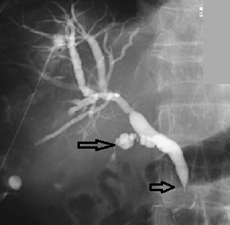

Radiology images An adenocarcinoma, probably of pancreatic origin, obstructs the common bile duct (arrowhead). The cystic duct is also infiltrated (arrow).